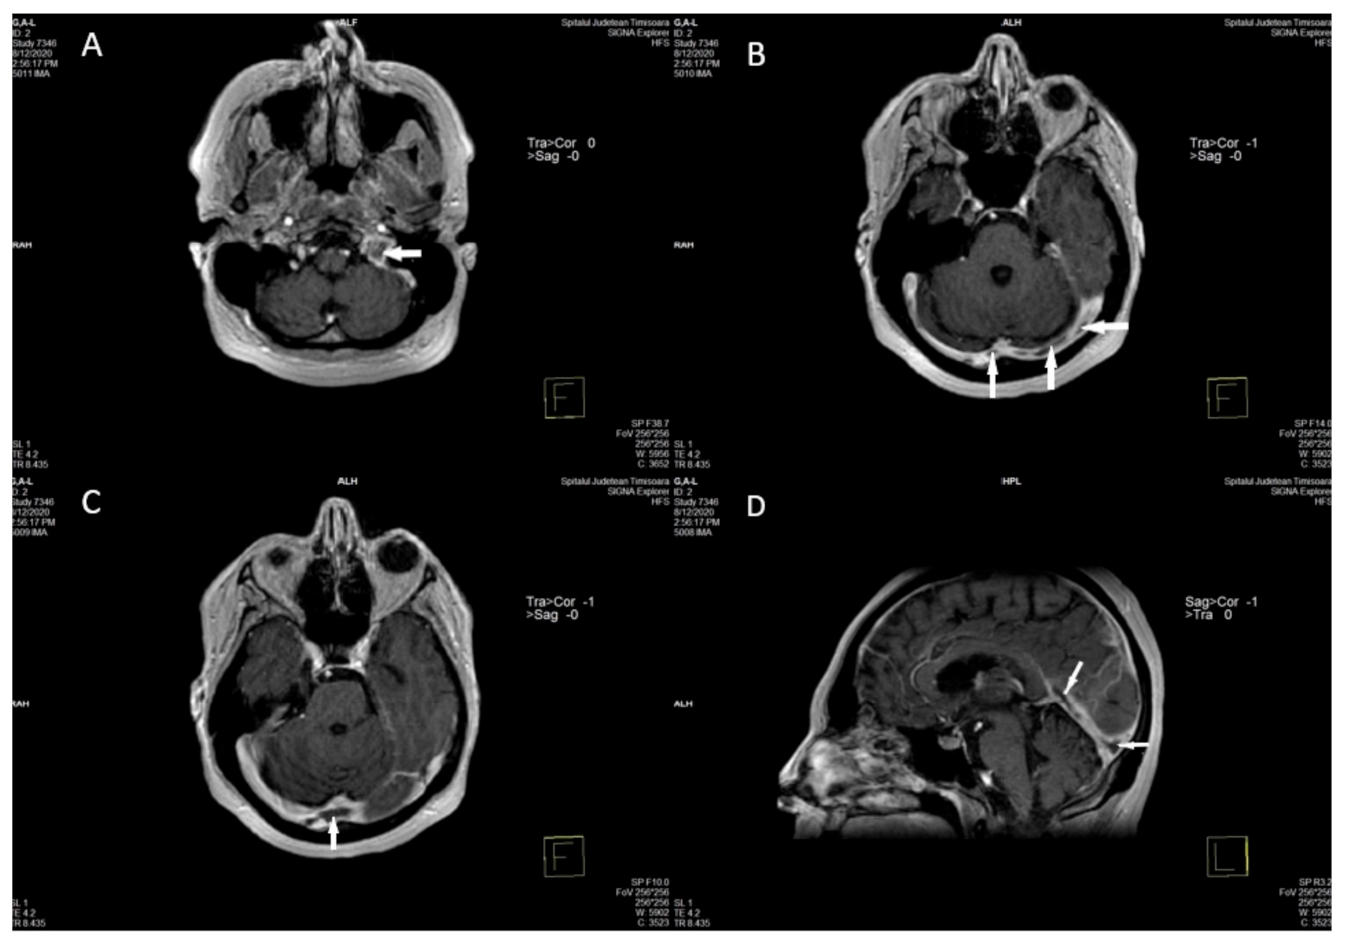

2.2. Imaging